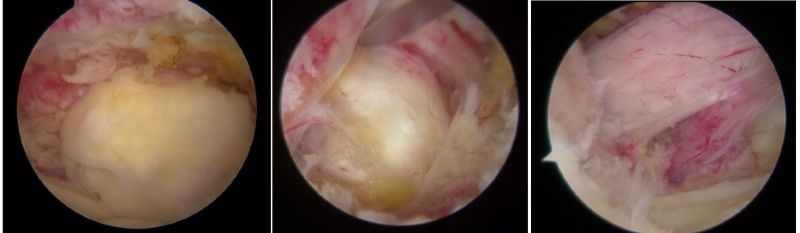

骨科内镜下的腰椎组织

近年来,随着脊柱内镜技术突破性发展,以"精准减压、最小侵袭"为核心理念的微创术式已成为60%以上腰椎手术患者的优先选择,特别是合并多种疾病、无法耐受开放手术的高龄患者。相较于传统开放式手术需大面积剥离肌肉组织、损伤脊柱稳定性的弊端,该技术通过直径仅7-8毫米的骨科内镜工作通道,在局部麻醉下借助高清内镜可视化系统精准定位病灶,实现了"靶点精准治疗"的突破性进展。

UBE是unlateral、biportal、endoscopic三个英文单词的首字母,也就是“单侧双通道脊柱内镜”。临床上简称为:“UBE”。其技术的核心是双通道:一个是内镜通道,另一个是器械操作通道,两处皮肤切口各仅约0.8cm。与传统开放手术相比,它借助天然解剖间隙建立微创工作通道,解除神经压迫。对椎旁肌肉损伤较小,且能够最大程度地保留完整的脊柱结构,维持了术后脊柱的稳定,具有创伤小、出血少、恢复良好、并发症少、费用低等优点,大幅提升了手术的效率和安全性。